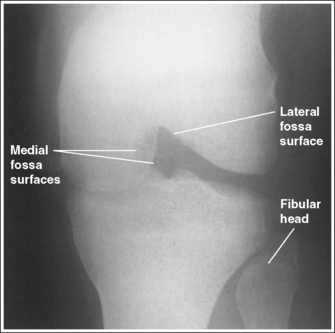

The lateral knee compartment is narrower than the medial knee compartment. The patient's knee demonstrates a valgus deformity.

The medial knee compartment is narrower than the lateral knee compartment. The patient's knee demonstrates a varus deformity.

• Analysis of joint space narrowing. On an AP knee projection with adequate positioning, joint space narrowing is evaluated by measuring the medial and lateral aspects of the knee joint, which are also referred to as compartments. The measurement of each of these compartments is obtained by determining the distance between the most distal femoral condylar surface and the posterior condylar margin of the tibia on each side. Comparison of these measurements with each other, with measurements from previous images, or with measurements of the other knee determines joint space narrowing or a valgus or varus deformity. In a valgus deformity the lateral compartment is narrower than the medial compartment; in a varus deformity the medial compartment is narrower (see Images 56 and 57). Precise measurements of the compartments are necessary to ensure early detection of joint space narrowing and are best obtained when the knee joint space is completely open. If an inaccurate central ray angulation was used for an AP knee projection, the knee joint is narrowed or obscured, the intercondylar eminence and tubercles are foreshortened, and the tibial plateau is demonstrated.